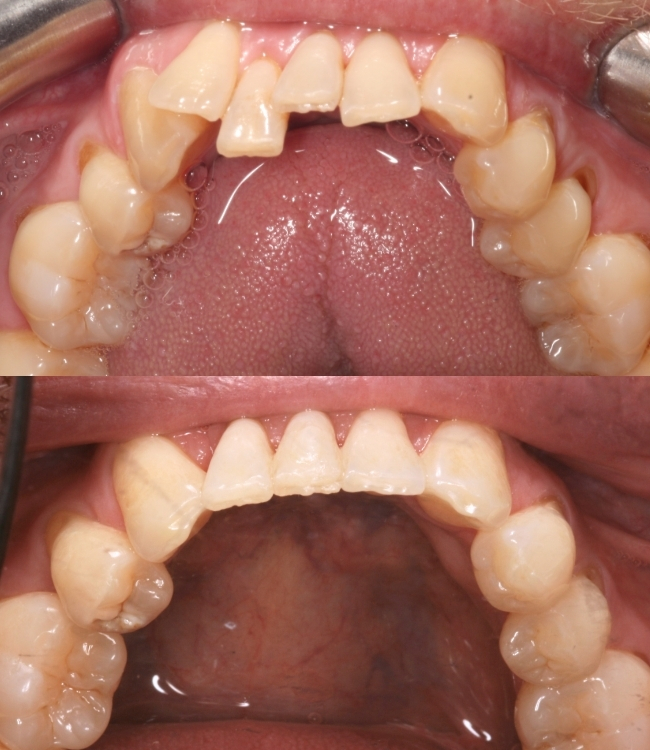

Jonathan came to us wanting to make a change – he had crowding in his lower front teeth and one tooth was pushed forward and twisted, making his smile look uneven.

1. Removing the crowded lower tooth – One twisted lower tooth was in the way, so removing it created the space needed to straighten the rest.

2. Straightening with Invisalign – With aligners worn as advised, the teeth gently moved into a much straighter, neater position.

4. Composite bonding to perfect the final look – Added small, precise touches to tidy edges and shapes, creating a smooth, natural finish.

The result? A bright, perfectly balanced smile.

As you can see for yourself, the end result is fantastic, and understandably, Jonathan was delighted – he’s now able to smile with confidence and easily keep his teeth clean, which is great for his gum health.